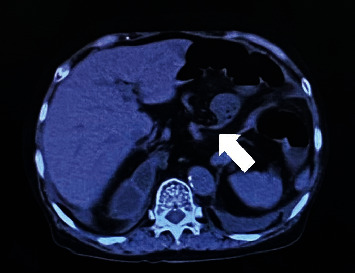

IV 型食管裂孔疝的特点是胃和相关器官(如脾脏、大肠、小肠和胰腺)通过食管裂孔疝出。这是一种相对罕见的食管裂孔疝,有时因胃嵌顿、胃内翻和绞窄而需要进行急诊手术。其中,小肠梗阻极为罕见,需要手术治疗。我们报告了一例因回肠嵌顿食管裂孔导致小肠梗阻而入院的 83 岁妇女的病例,该患者接受了紧急腹腔镜手术。

Type IV hiatal hernia of the esophagus is characterized by herniation of the stomach and associated organs, such as the spleen, large and small bowel, and pancreas, through the esophageal hiatus. It is a relatively rare form of hiatal hernia that sometimes requires emergency surgery due to gastric incarceration, volvulus, and strangulation. Of these, small bowel obstruction is extremely rare and requires surgery. We report the case of an 83-year-old woman who was admitted to the hospital for small bowel obstruction caused by an ileum that had incarcerated the esophageal hiatus; emergency laparoscopic surgery was performed.